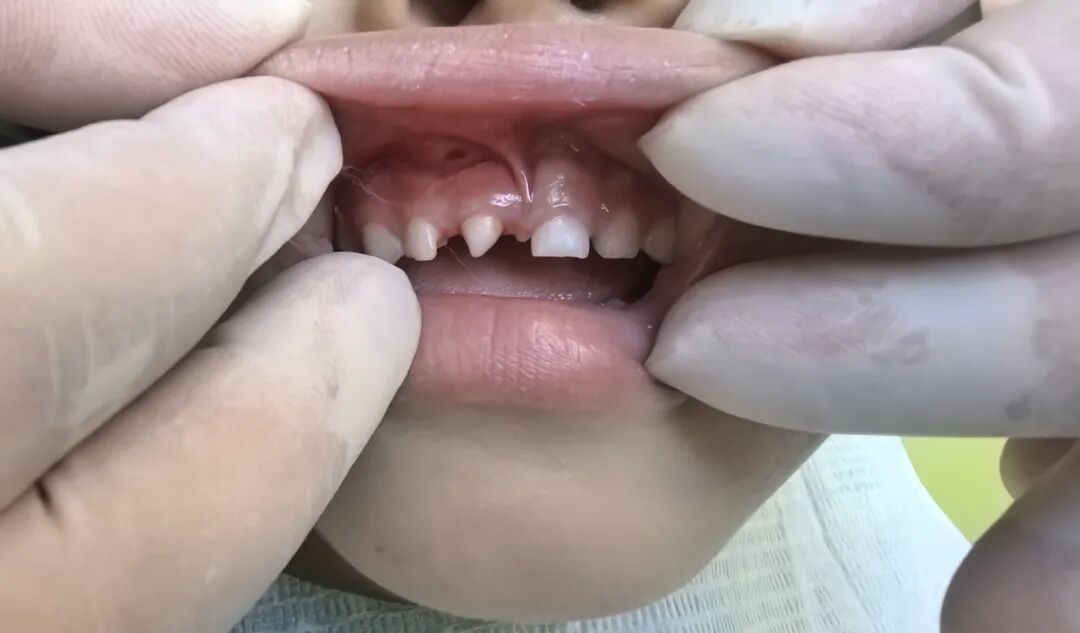

近日,我院口腔科与麻醉科的共同协作下顺利完成首例儿童镇静下口腔治疗。5岁女童因多生牙曾多次到我院口腔科寻求治疗仍无法取得患儿配合。随后在口腔科程敬雨主任与麻醉科唐国值主任的沟通下,最终确定治疗方案:在门诊行镇静监护下进行口腔治疗,家长表示理解并完全赞同实施该方案。

术前口腔CBCT检查